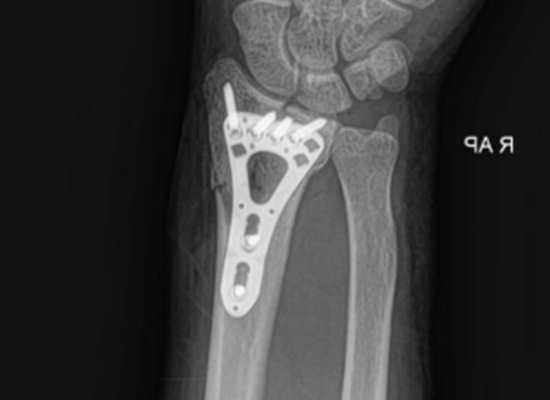

At Tlalixtac de Cabrera State Hospital, Mexico, a distal radius fracture surgery was successfully performed using a VA Distal Radius Locking Plate provided by CZMEDITECH, a leading orthopedic implant manufacturer from China.

The operation, led by Dr. José Alfredo Rios Melchor, achieved precise anatomical alignment and rapid patient recovery — highlighting how modern trauma fixation systems are improving outcomes across Latin America.

Postoperative evaluation revealed excellent alignment, stable fixation, and early joint motion.

Implant Used:

VA Distal Radius Locking Plate (25.5 mm, 2-hole)